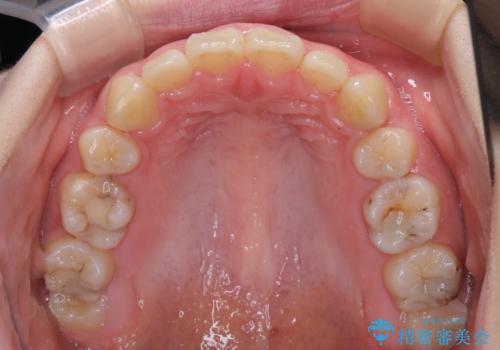

- 口元の突出感を気にして来院された患者様です。

上下左右の第一小臼歯4本を抜歯して口元を下げる治療計画としました。

目立たない装置が希望であったため、上顎が裏側装置である、ハーフリンガル装置を選択されました。

当初予定では3年以上かかるとお伝えしておりましたが、スムーズに歯列が整い、2年強で終了することができました。